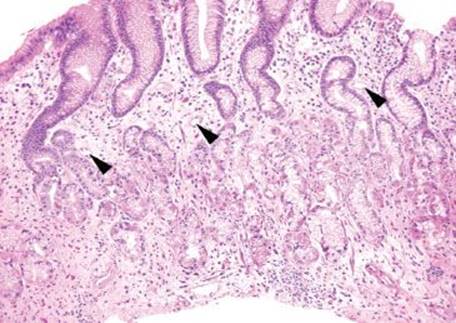

Figure 2.207 Vascular changes, portal hypertensive gastropathy (PHG). This example illustrates a vascular pattern of injury: a number of congested mucosal vessels are seen in a background of reactive gastritis/gastropathy. This patient was known to have cirrhosis and portal hypertension; these histologic findings support the clinicopathologic diagnosis of PHG.

Figure 2.210 PHG. At low power, the predominant finding is that of reactive gastritis/gastropathy pattern of injury: gastric foveolar mucin cell depletion, a corkscrew-like appearance of the foveolar epithelium, lamina propria edema, and little to no inflammation. The reactive gastritis/gastropathy pattern can be a red flag to a variety of additional diagnoses. In this case, scattered congested vessels are seen (arrowheads).